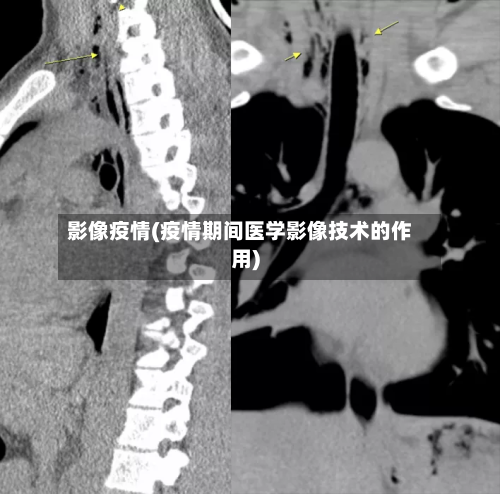

影像疫情(疫情期间医学影像技术的作用)